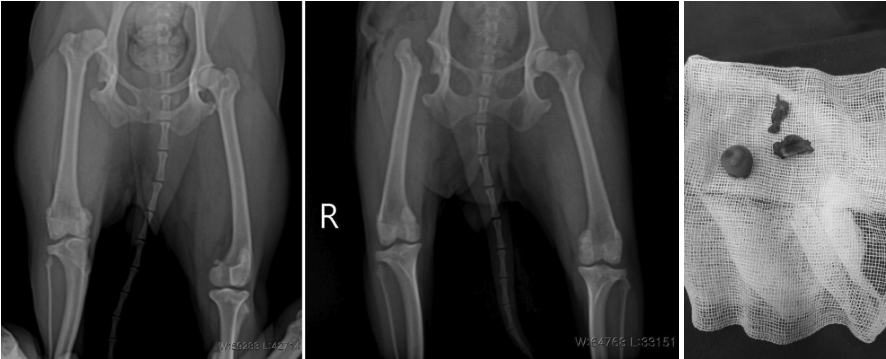

2) FHO (대퇴골두 절제술)

관절 통증의 원인이 되는 대퇴골두(공 모양의 뼈 부분)를 제거하는 수술입니다. 관절 구조는 남지 않지만, 마찰을 일으키는 부위를 없애기 때문에 통증 개선 효과가 크며, 소형견 또는 체중이 가벼운 중형견에서 좋은 결과를 보입니다. 관절 변형이 심하거나 만성 관절염이 동반된 경우에 선택되는 수술입니다.

FHO 수술 전/후 방사선 사진 / 출처: 24시온숲동물의료센터